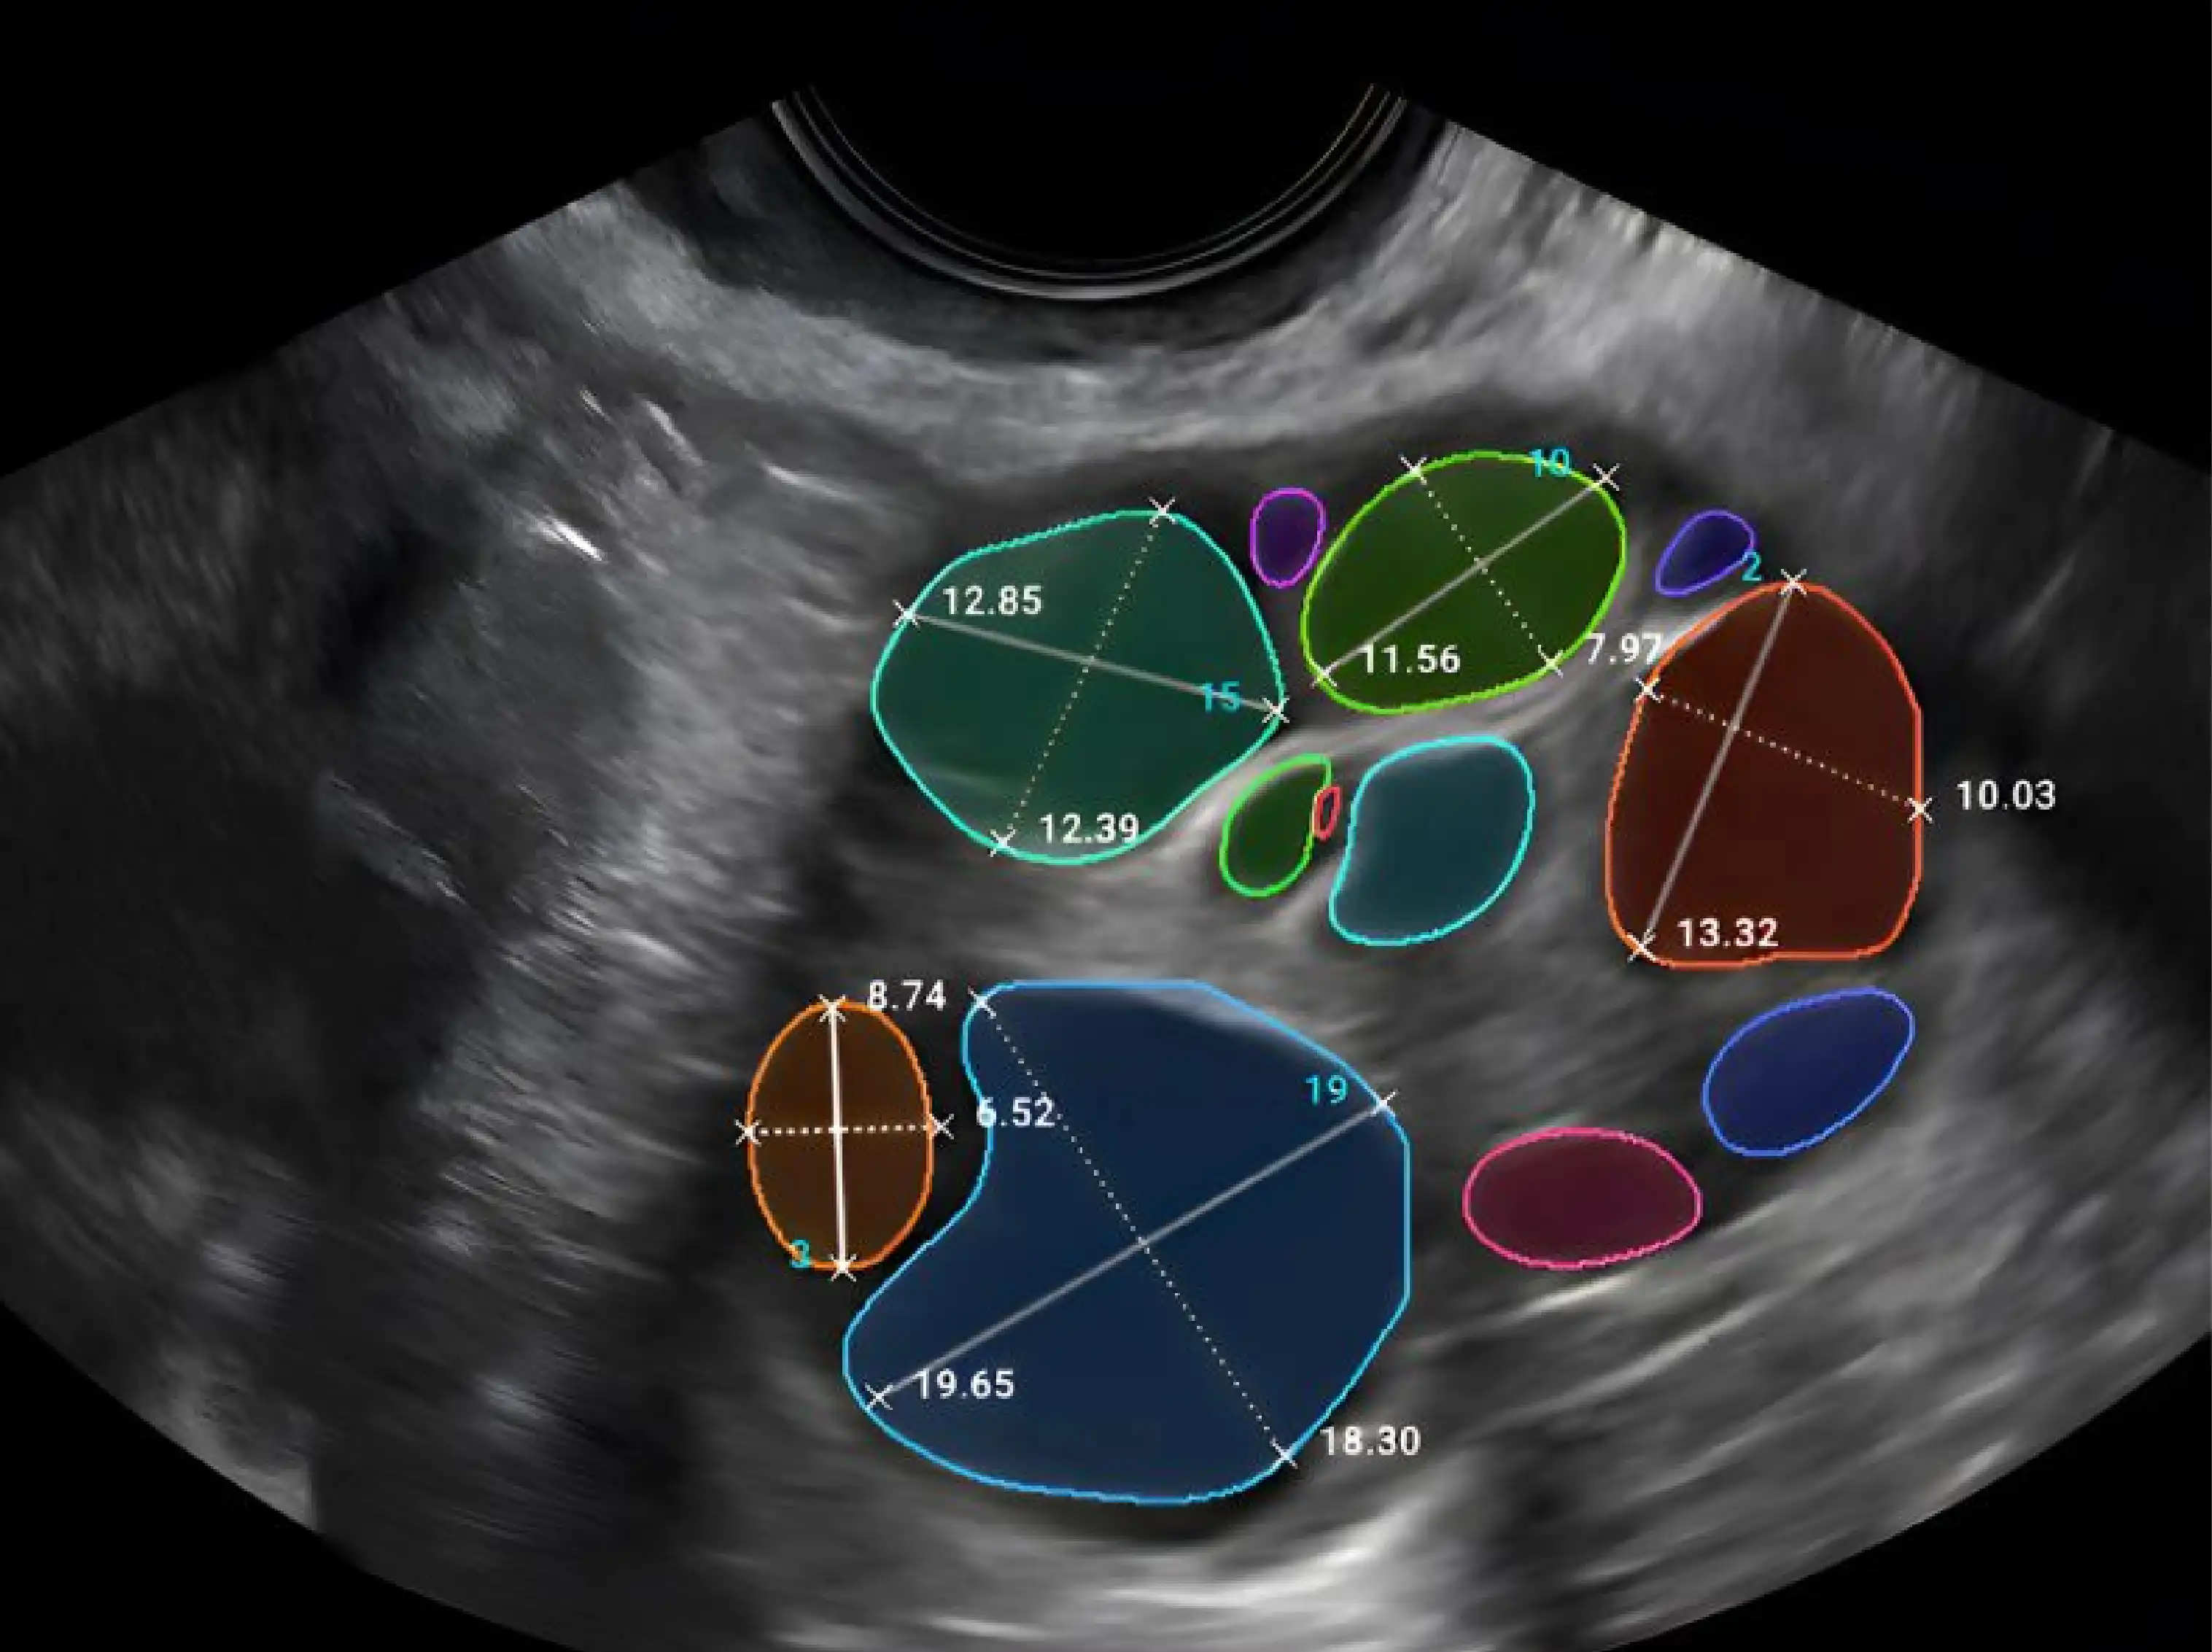

التلقيح الصناعي (IVF)

التلقيح الصناعي (IVF) | المملكة العربية السعودية